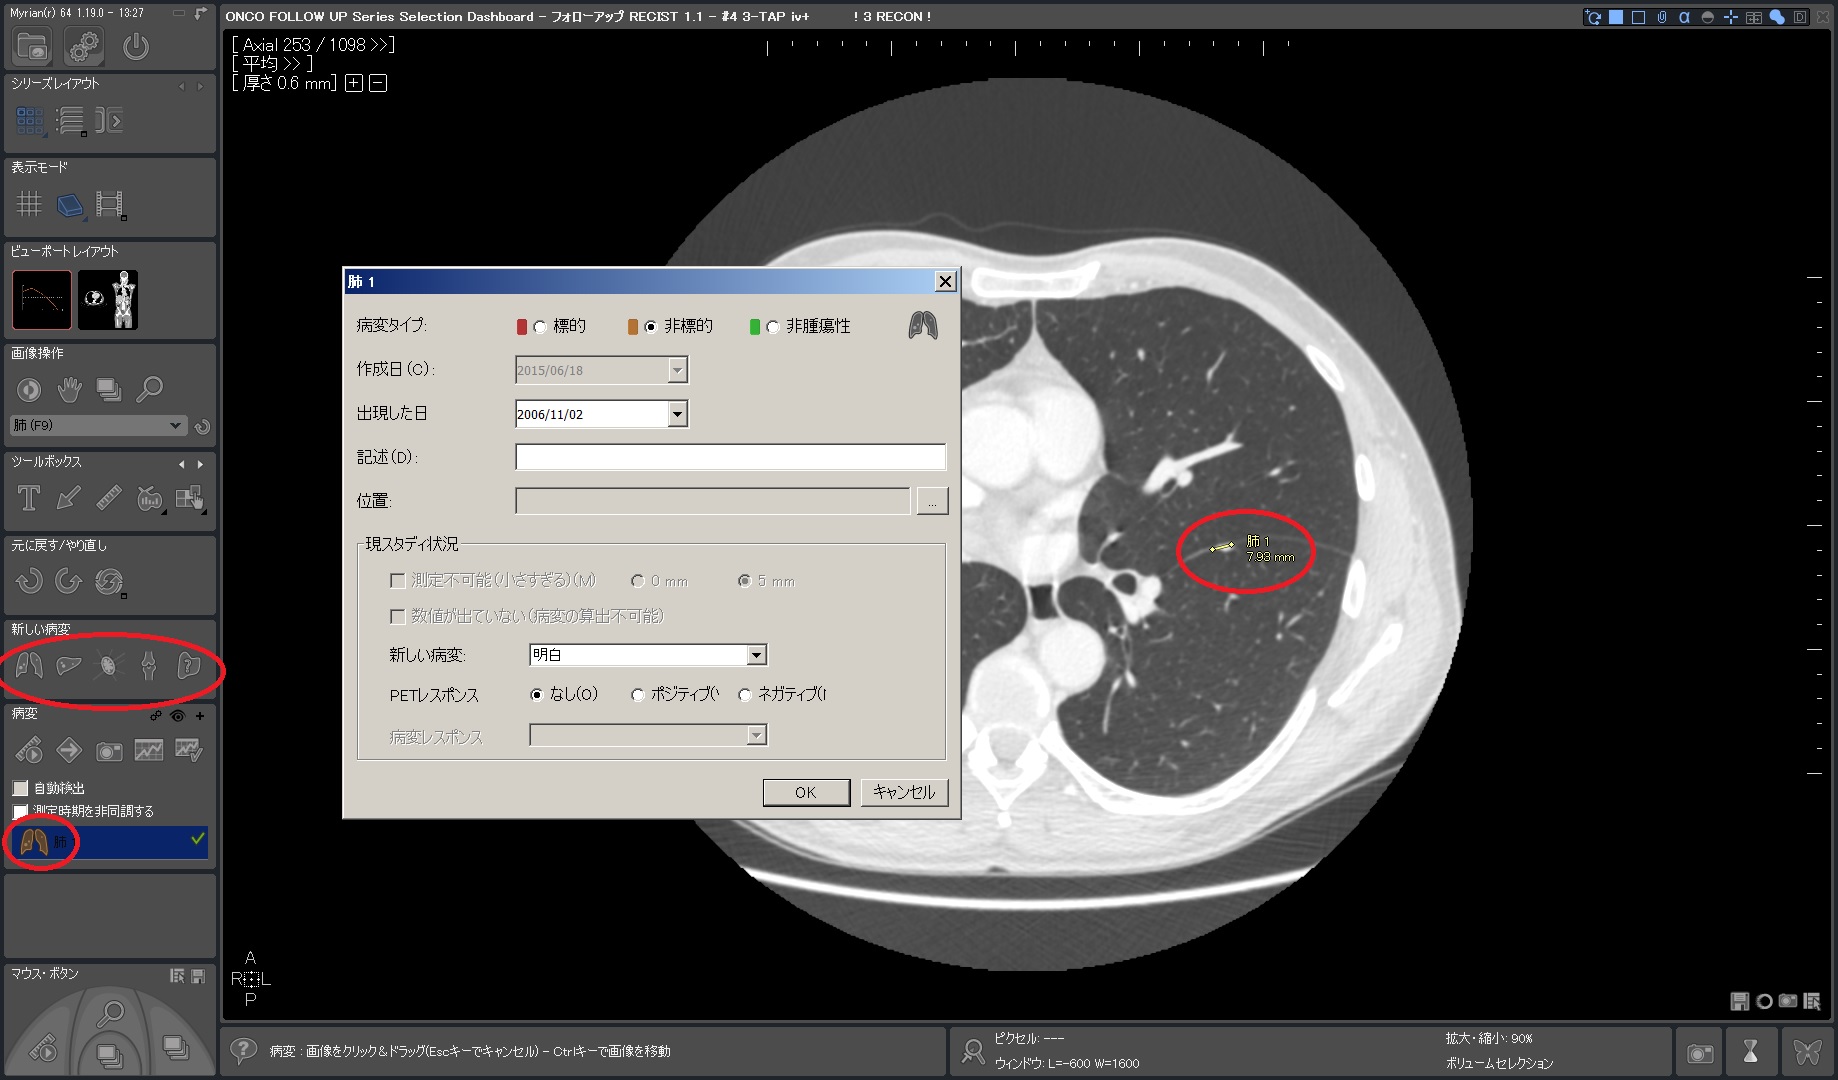

Myrian®XL-Onco 腫瘍の経時的フォローアップ・アプリケーション

効率的なフォローアップのための理想的なソフトウェア

フォローアップに必要なすべてのステップは自動化されています。 ベースライン作成後、次のタイムポイントでは自動的に非剛体レジストレーションが行われ、高速な検査比較が可能です。必要に応じて自動で国際評価基準(RECIST1.0,1.1)に沿った治療レスポンスが計算され、PACSへ転送されます。そし検査レポートも自動作成されます。

※腫瘍以外にも様々な部位/組織の経時的な評価にご利用できます。お問い合わせください。

| 2.ターゲット/非ターゲット 各種ROIを計測 、承認 |

|

|

|

| 3.次のタイムポイントでは自動でロードされ、正確に位置合わせたROIを 素早く計測 |

|

|

|

|